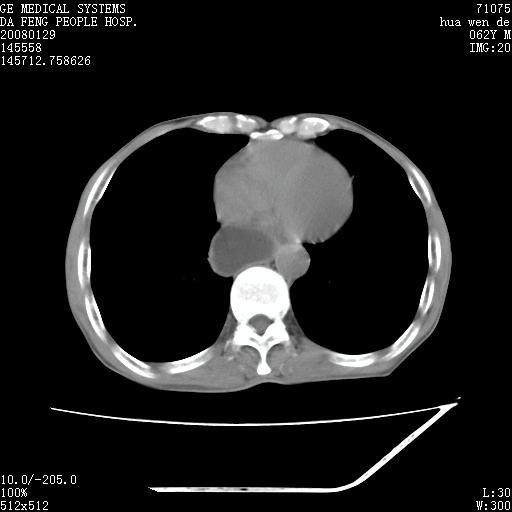

男性,67岁。作肺部检查时发现

右肺脓肿 胸腔胃

考虑1、右肺周围型肺癌可能性大。

2、贲门失迟缓症可能,建议钡餐检查。

考虑:胸腔胃并支气管瘘(并发肺炎,肺脓肿形成)。

理由:1、右上肺内病灶,空洞形成,有液平。

2、肺内多处炎症。

3、前段肺内炎症,支气管引流通畅,与肿块无关系。

1.整个食管扩张,未见明显占位性病变,贲门区亦未见明显占位病变,考虑:贲门失驰缓症;

2.右上肺病变边缘可见毛刺,囊壁厚度不均匀,周围境界较清楚,未见炎性渗出性影,右上肺外带可见片状影,边缘不清,考虑:肺癌伴空洞形成、右上肺炎。

食管全程扩张,壁均匀不厚,喷门失弛缓症

右上肺空洞可见液平,临近肺野磨玻璃密度,考虑1.结核2.脓肿